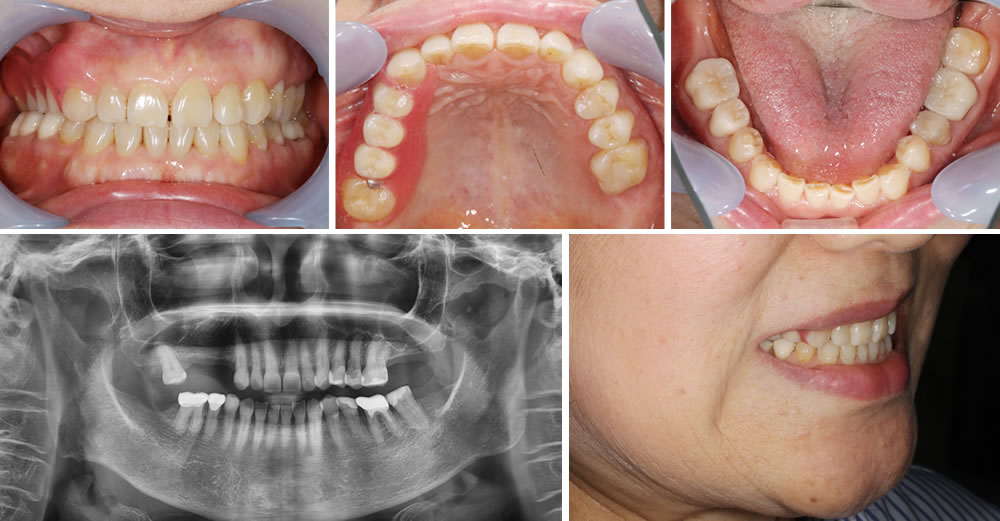

ノンクラスプデンチャーの装着・治療完了

インプラント治療ではなく、右上欠損部をノンクラスプデンチャーで治療しましたが、右上7番を保存することができた事によって、ノンクラスプデンチャーが前後の歯でしっかりと安定した状態を作る事ができました。それによって、患者さんのしっかり噛みたいという要望にも応える事ができ、非常に満足されていました。

入れ歯の沈み込み防止のために、最後方の歯には強度のあるメタルレストを使用させて頂きましたが、取り外しのできるものでこれぐらいなら気にならないとの事でご了承頂きました。歯に引っかける部分に金属を使用していないので、装着時も目立たずに見た目も気にならないので嬉しいとおっしゃっていました。

| 年齢/性別 | 70代/女性 |

|---|---|

| 治療期間 | 8ヵ月 |

| 治療回数 | 18回 |

| 治療費 | 1,000,100円(税込) ※内ノンクラスプデンチャー費用 165,000円(税込) |

| リスクなど | ・部分的に強い力がかかると、入れ歯が破損する可能性があります。 ・経年的に入れ歯の適合度合いが悪くなる可能性があります。 |